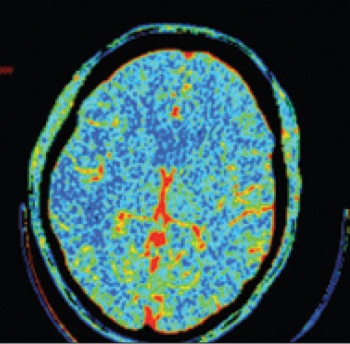

Strategies evoke the mismatch concept to identify tissue at risk. Both MRI (perfusion-diffusion) and CT perfusion (mean transit time-cerebral blood volume) have been used to identify the ischaemic penumbra. EPITHET24 (alteplase, three to six hours), DIAS,19 DEDAS20 and DIAS 221 (desmoteplase, three to nine hours) were all randomised clinical trials using MRI or CT perfusion to identify ischaemic penumbra and guide thrombolysis decisions.

See Figures 1(i)-3(ii) for images of a successful endovascular therapy case.